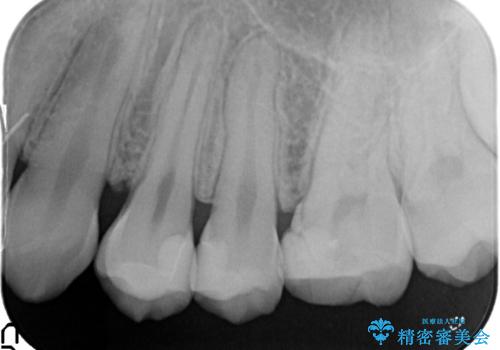

精密なむし歯の治療 セラミックインレー

- 定期健診にてむし歯を認めた患者さまです。

笑った時に見える部分だったためセラミックインレーにて修復しました。

保険治療で使える材料には制限があり、見た目だけでなく精度でも劣ります。当院でのセラミックインレーは歯とのつなぎ目を拡大鏡で確認して精度高く仕上げるため、むし歯のリスクを限りなく少なくできるよう治療します。